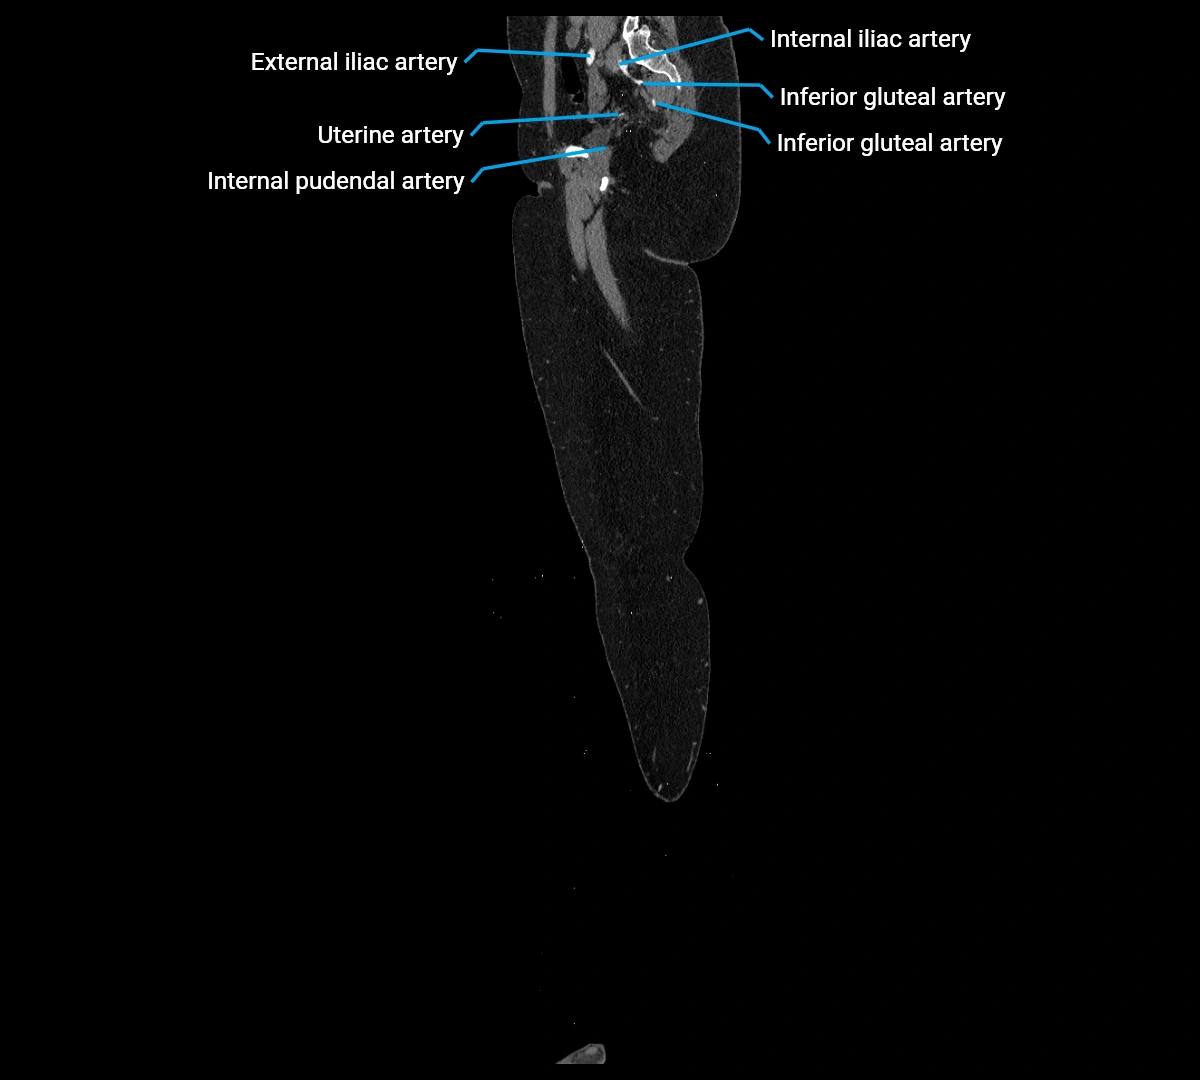

CT images

image

Contrast-enhanced CT (CTA):

• Gold standard for abdominal aortic imaging

• Provides excellent detail of lumen, wall, aneurysm, thrombus, and branch vessels

• Multiplanar and 3D reconstructions help in aneurysm measurement, stent graft planning, and dissection evaluation